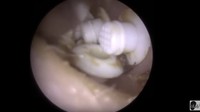

Nah, kalau ini bukan kotoran telinga. Tapi filter alat bantu pendengaran yang bersarang di dalam telinga secara tidak sengaja. (Foto: YouTube)